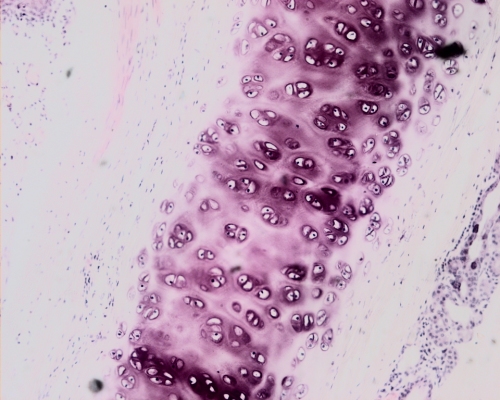

Fig 073-005

Hyaline cartilage